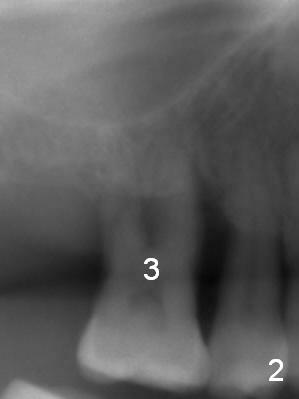

4 mm Bone, 6 mm Gingiva

A 44-year-old man requests an implant at #3 because of mobility. It appears that the bone height decreases from 6 mm (Fig.1,2: 3 years ago) to 4 mm (Fig.3,4, recently). After extraction and Clindamycin treatment, take PVS impression of the socket. Use initial drill with drill stopper of 3 mm and round burs with stoppers from 4 to 5 mm. If the buccal (B) and palatal (P) plate defect is severe, use a regular implant. Otherwise use an extra wide one. The advantage of the latter is length as short as 6 mm vs. 8 mm for the regular one. For the latter, 2 mm of the implant will be in the sinus (Fig.4 red box), 4 mm in bone (pink box) and 2 mm in the socket (orange box; to be surrounded by bone graft). Since the gingiva is 6 mm (Fig.4 green box), an abutment with 6 mm cuff should be chosen. To reduce occlusal interference, select abutment height 4 mm.